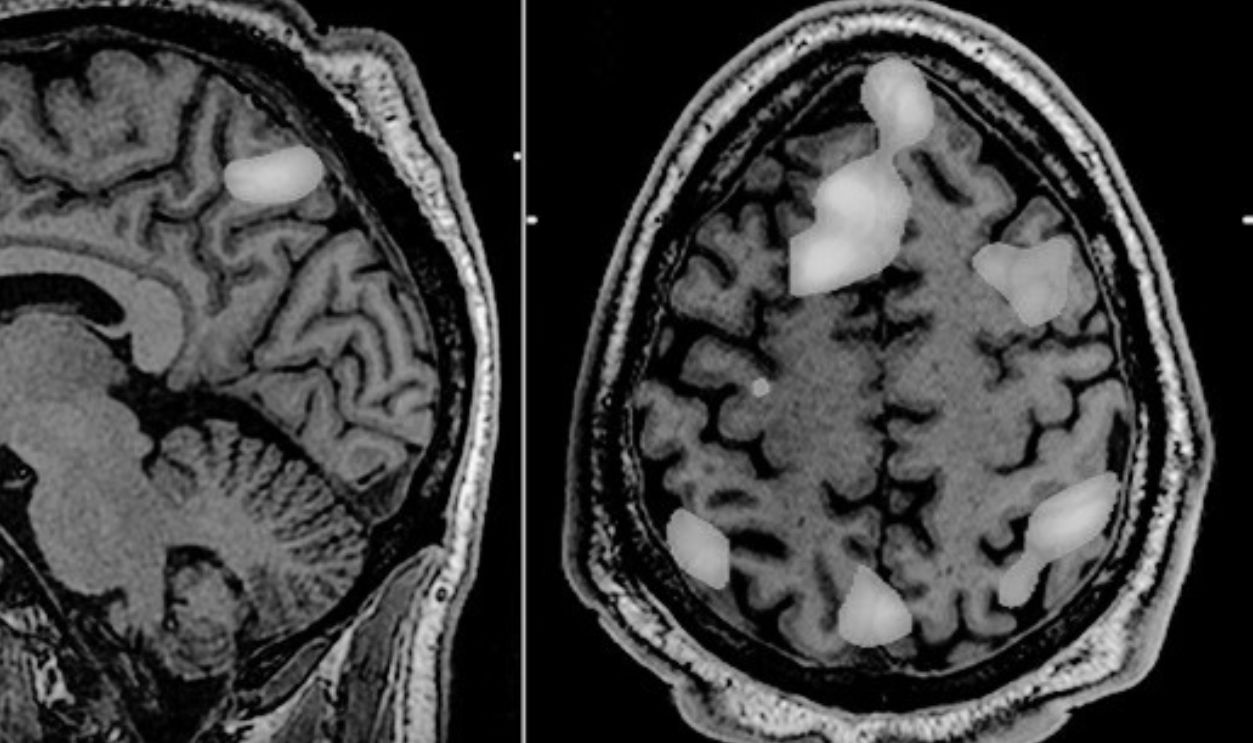

Neuroimaging Changes Everything

Technology for studying the brain also was moving forward with all these discoveries. The development of PET (positron emission tomography) and fMRI (functional magnetic resonance imaging) allowed researchers to observe brain activity in living humans. This was a big step forward, as it overturned decades of inference-based guesswork, enabling direct testing of how thoughts, emotions, and decisions correspond to neural activity.